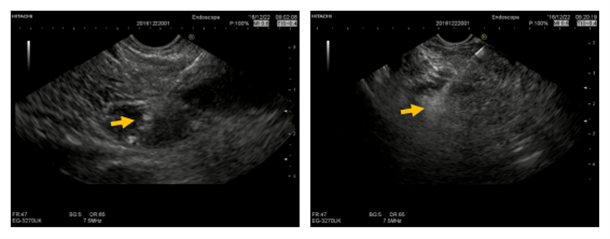

2016.12.22.行FNA穿刺活检与无水乙醇消融术,将穿刺针准确刺入。病变内留取样本送检,超声监控下注射无水乙醇1.6ml。

消融4日后复查超声内镜后表现为中等偏高回声病灶,血管消失